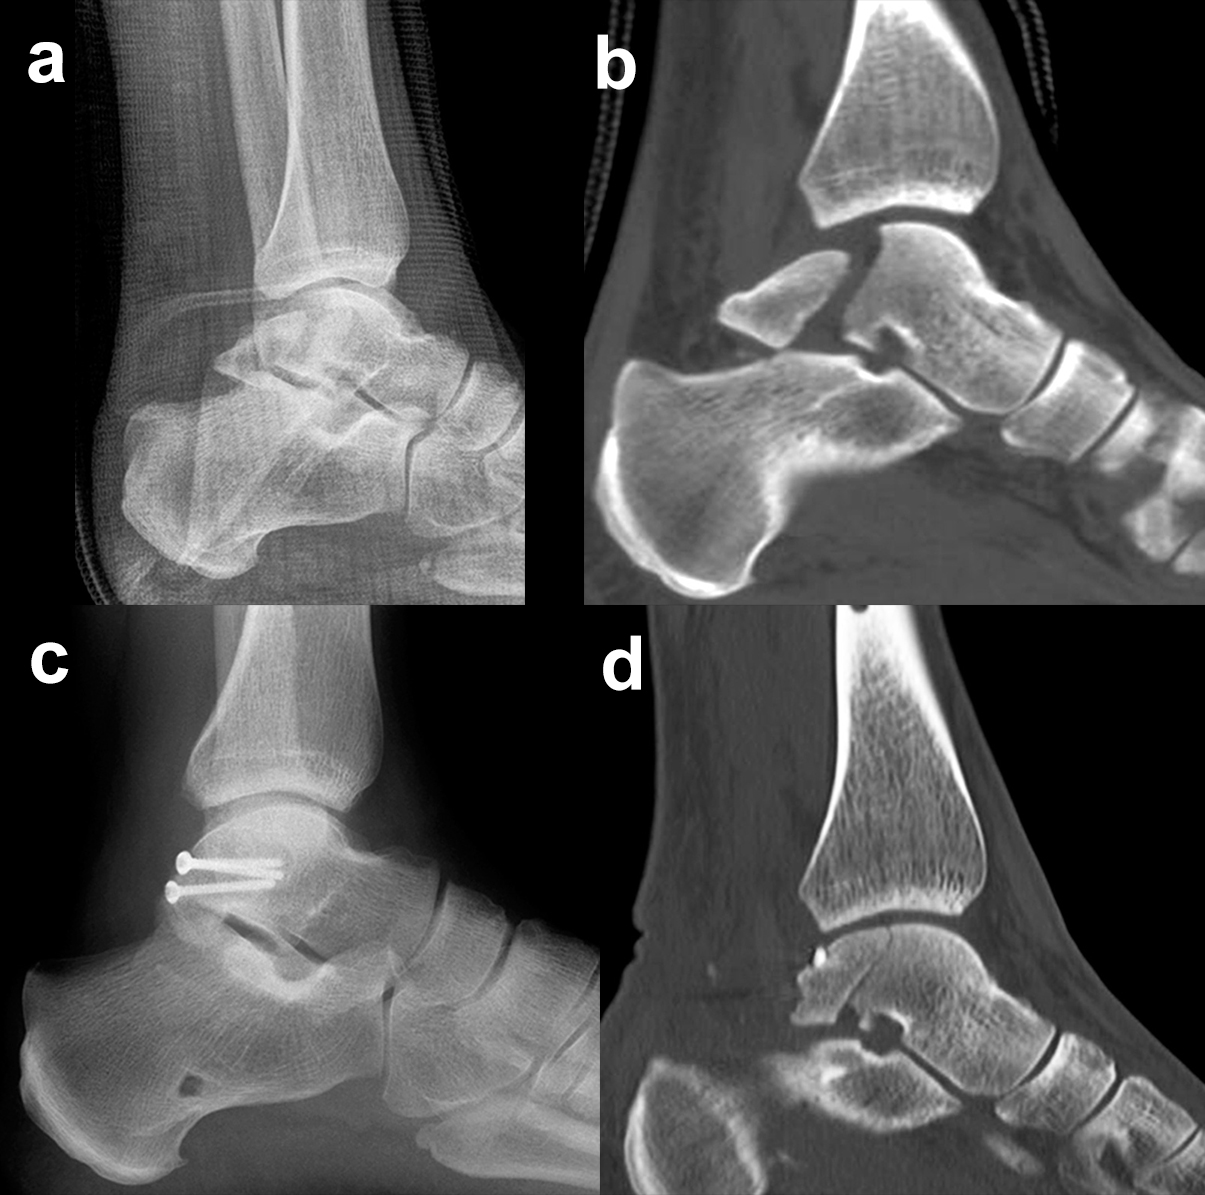

Prinzipiell werden konventionelle Röntgenaufnahmen vom OSG in 2 Ebenen (a.p. in 20° Innenrotation, „Mortise View“, und lateral) angefertigt (Abb. 1a, b). Zusätzlich können spezielle Projektionen wie die Canale oder Brodén-Aufnahme hilfreich sein, wurden in der klinischen Routine aber durch das CT oder DVT weitgehend verdrängt.

Bei in den konventionellen Aufnahmen nicht sicher auszuschließender Talusfraktur bzw. zur genauen Darstellung der Dislokation bei Taluskorpus- oder Talushalsfraktur sollte die Indikation zur CT-Diagnostik großzügig gestellt werden (Abb. 1 c, d). Insbesondere dient die CT-Diagnostik zur genauen Evaluierung der Frakturmorphologie und OP-Planung sowie auch zur Vermeidung möglicher übersehener peripherer Talusfrakturen 4.

Frakturen des Proc. fibularis tali werden im konventionellen Röntgenbild nicht selten übersehen. Sie entstehen häufig nach schweren Distorsionen bzw. im Rahmen subtalarer Luxationen. Eine CT-Kontrolle nach geschlossener Reposition subtalarer Luxationen ist daher obligat (Ab. 15). Der Proc. fibularis tali ist über den anterolateralen Zugang oder schräg verlaufenden Ducroquet-Ollier-Zugang gut zu erreichen. Die subtalare Arthroskopie über anterolaterale und posterolaterale Portale bietet wie bei intraartikulären Kalkaneusfrakturen die Möglichkeit der exakten Kontrolle der geschlossenen Reposition bei einfachen Frakturformen 35. Nach anatomischer Reposition und temporärer Fixierung mittels 1,0 Kirschnerdraht erfolgt die Osteosynthese mittels Kleinfragmentschrauben (2,7 bzw. 3,5 mm), die unterhalb der Knorpel- Knochengrenze eingebracht werden und für eine ausreichende Stabilität sorgen (Abb. 16). Kleinere, nicht anatomisch refixierbare Fragmente, oder Fragmente mit starker Knorpelkontusion werden vorzugsweise exzidiert (Abb. 17). Gleiches gilt für Frakturen des Proc. posterior tali zur Vermeidung einer posttraumatischen Arthrose 23736.